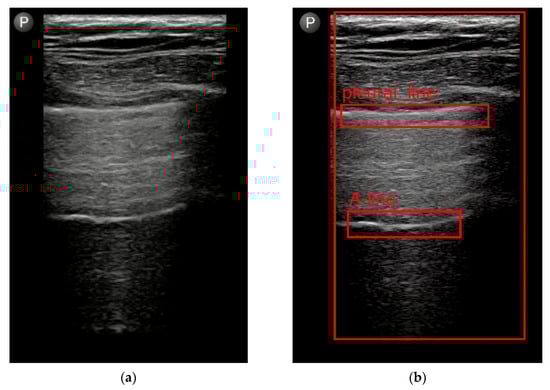

- Jaščur, M.; Bundzel, M.; Malík, M.; Dzian, A.; Ferenčík, N.; Babič, F. Detecting the Absence of Lung Sliding in Lung Ultrasounds Using Deep Learning. Appl. Sci. 2021, 11, 6976. [Google Scholar] [CrossRef]

- Hliboký, M.; Magyar, J.; Bundzel, M.; Malík, M.; Števík, M.; Vetešková, Š.; Dzian, A.; Szabóová, M.; Babič, F. Artifact Detection in Lung Ultrasound: An Analytical Approach. Electronics 2023, 12, 1551. [Google Scholar] [CrossRef]